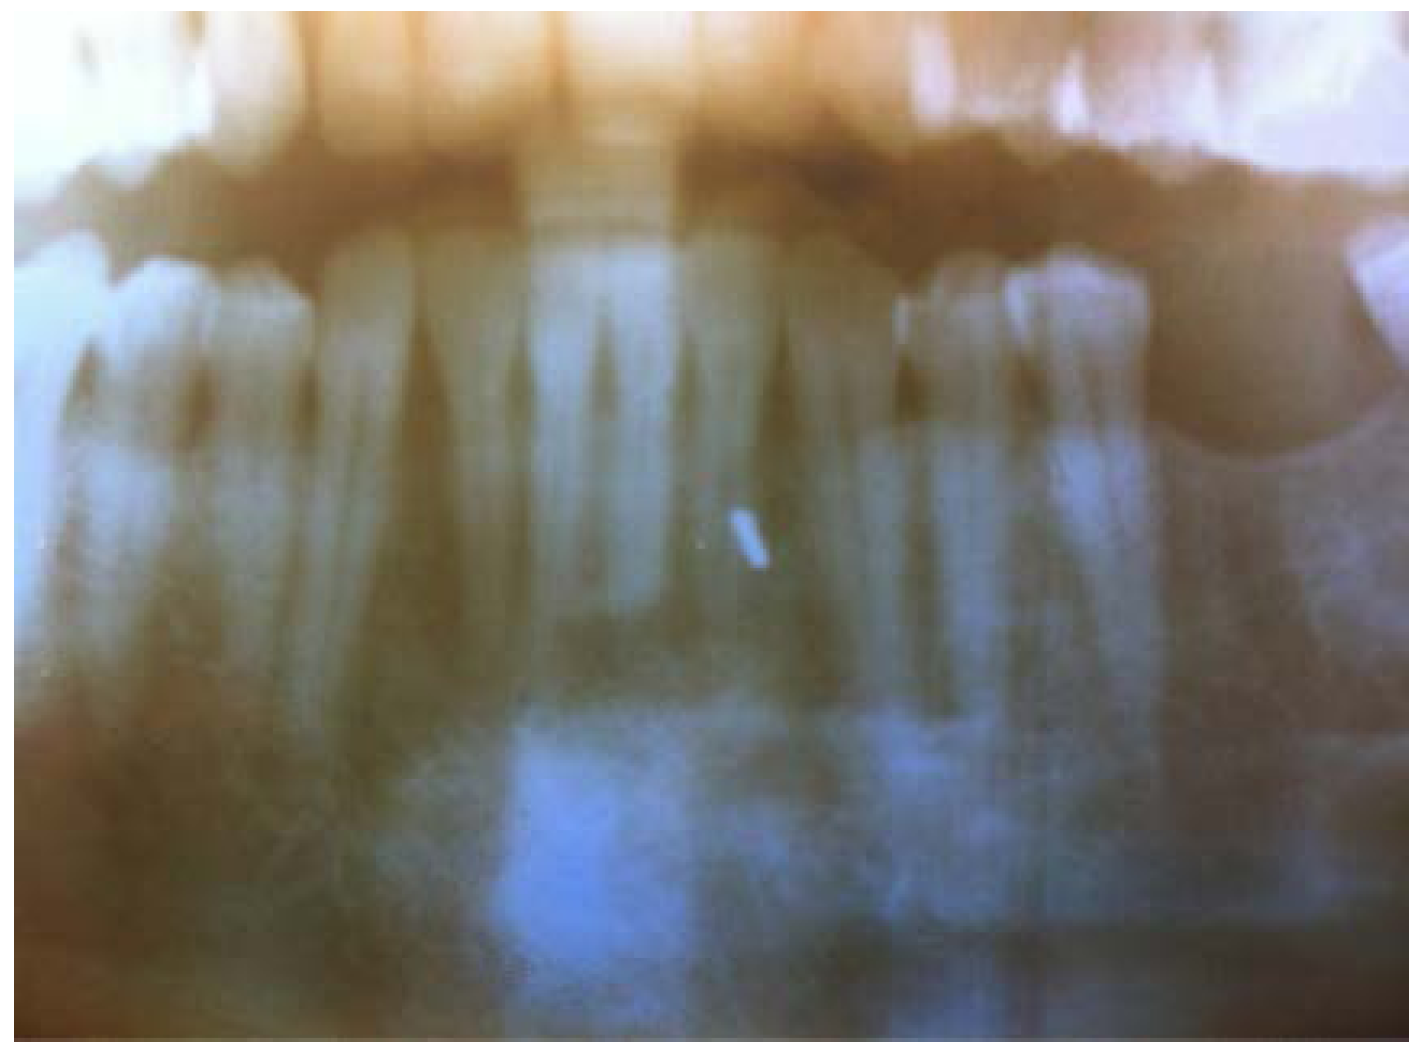

Later in the day, the dentist felt a slight hardness and slight pain upon palpitating the area. By the next day, the swelling had progressed slightly and the dentist felt a slight pain upon palpitation or any movement, such as chewing Figure 1 and Figure 2. He did not think that the small piece of bur was lodged in his chin. A decision was made to have radiographs taken, which included a panoramic and a peri-apical radiograph. Subsequent review of the radiographs revealed a radiopaque image consistent with a broken piece of the bur in the soft tissue of his chin, in the vestibule of the mandibular anterior left side Figure 3 and Figure 4.

Figure 3.

Panoramic X-ray.

Figure 4.

Pri-apical X-ray.